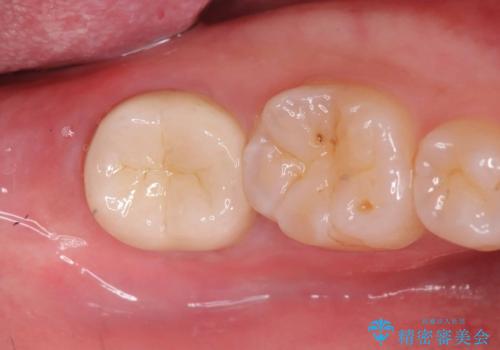

セラッミクインレー|オールセラミッククラウン|銀歯による二次カリエス|ラバーダムシート使用

銀歯の下の虫歯|オールセラミッククラウン|歯を長持ちさせるための治療|歯の神経を守る